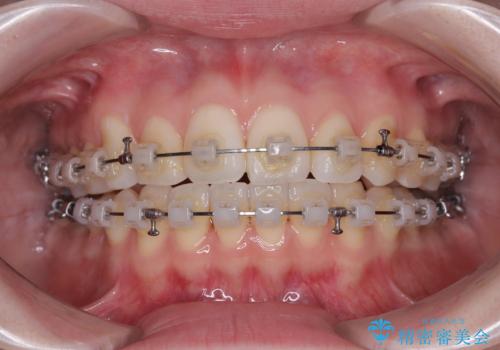

- クリアブラケット

- 1年6ヶ月

- 前歯のデコボコと、上下前歯が接触せずに前に飛び出していることを気にして来院された患者様です。

舌の突出癖が強く、それが原因で上顎歯列全体が前方に突出し、上下前歯が接触できない状態となっていました。

補助装置を用いて上顎臼歯を後方移動させ、歯列を整えながら前歯部の接触を図ることとしました。

舌の突出癖改善のためのトレーニングを指導しながら、ワイヤー装置にて矯正治療を行うこととしました。

舌のトレーニングは不十分でしたが、1年半ほどで治療を終えることができました。